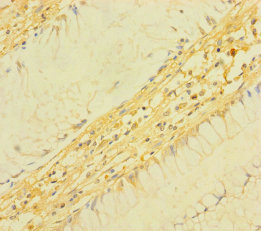

Immunohistochemistry of paraffin-embedded human colon cancer using CSB-PA023620LA01HU at dilution of 1:100